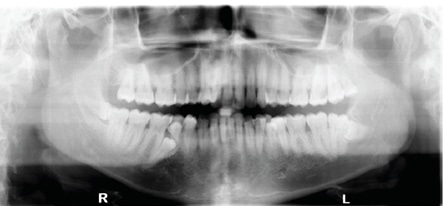

The periodontal classification was determined to be gradual-onset, generalized slight chronic periodontitis, modified by dentition (tooth anatomic factors). Clinical examination revealed no restorations and a large caries lesion on the distal of the upper left second molar, and incipient lesions on the occlusal surfaces of lower-left first and second molars, and lower-right second molar. Panoramic and full-mouth radiographic surveys revealed a lower-left impacted distomolar and lower-right supplemental premolar, and lower-right distomolar (Figure 2 and Figure 3), bringing the number of supernumerary teeth to 10. The patient was noted to have minimal supragingival calculus and generalized heavy subgingival calculus. The visual exam and a disclosing solution revealed only minimal plaque/biofilm accumulation.